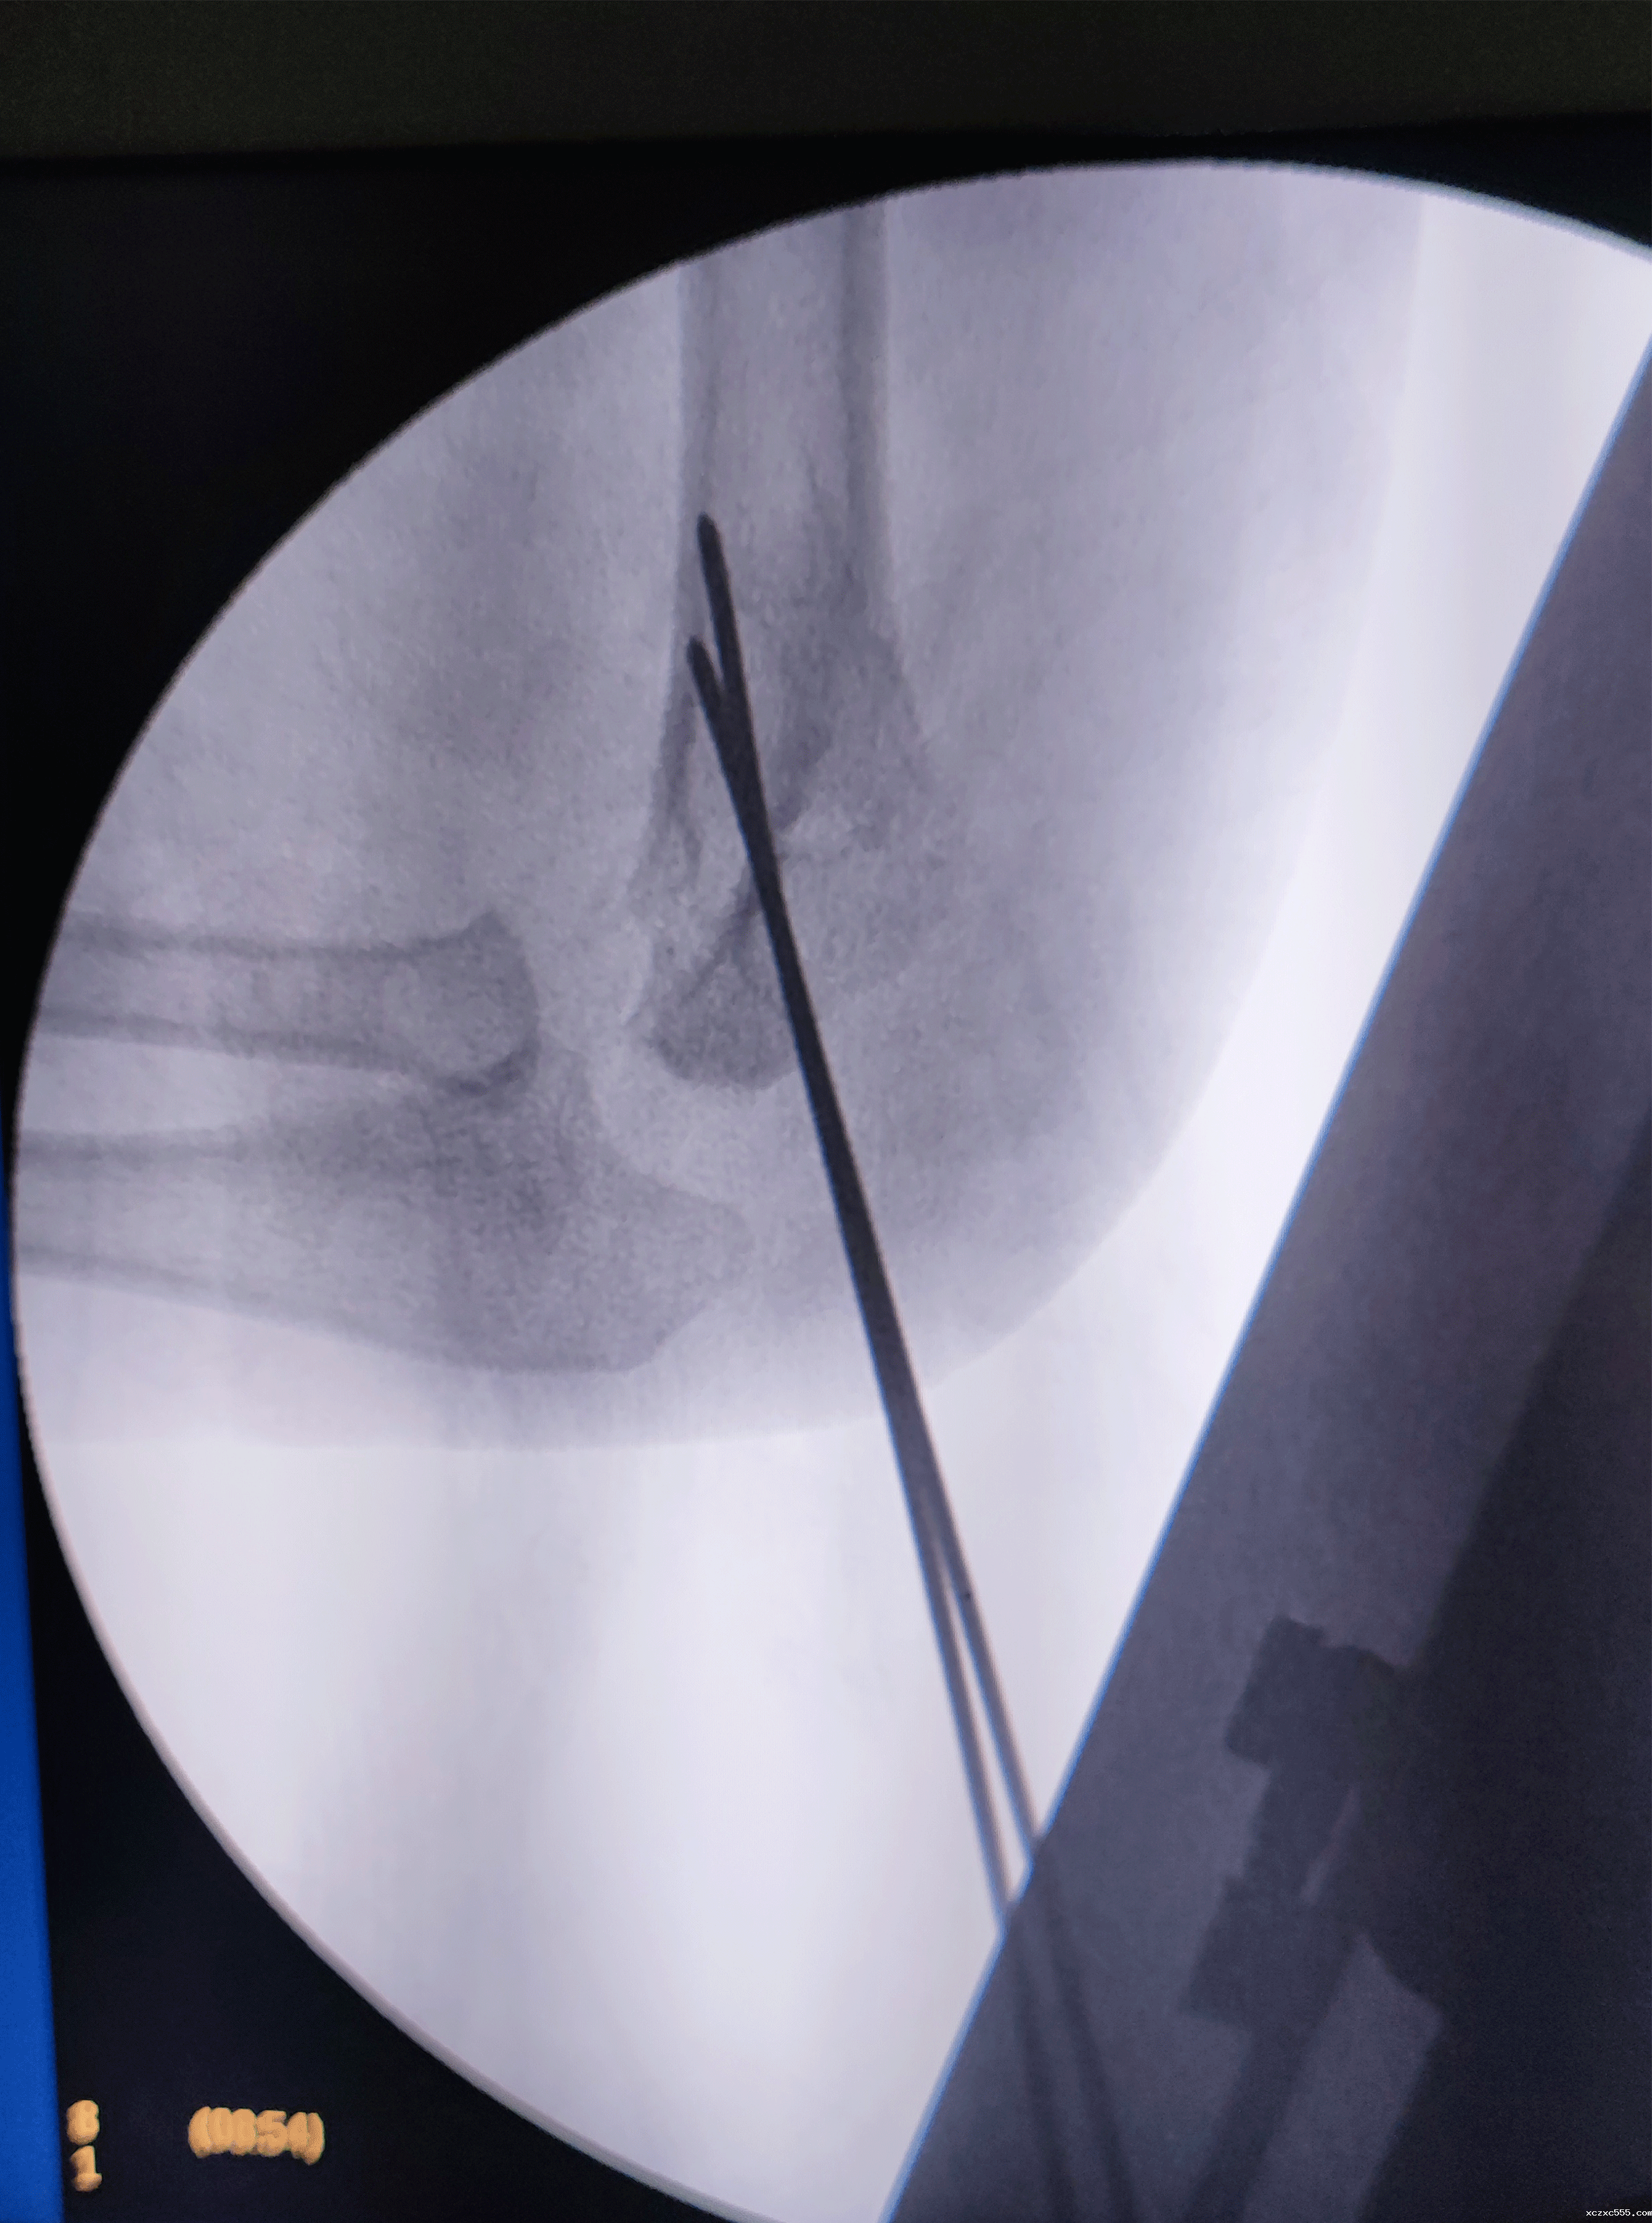

祝振华主任手术团队手术中

在征得患儿家属同意并完善相关术前准备后,祝振华主任带领我院小儿外科手术团队为小辰行全麻下肱骨髁上骨折闭合复位内固定手术。整个手术仅用时20分钟,术中几乎无出血,术后予以支具外固定。

术后X线显示:小辰肱骨髁上骨折位置复位